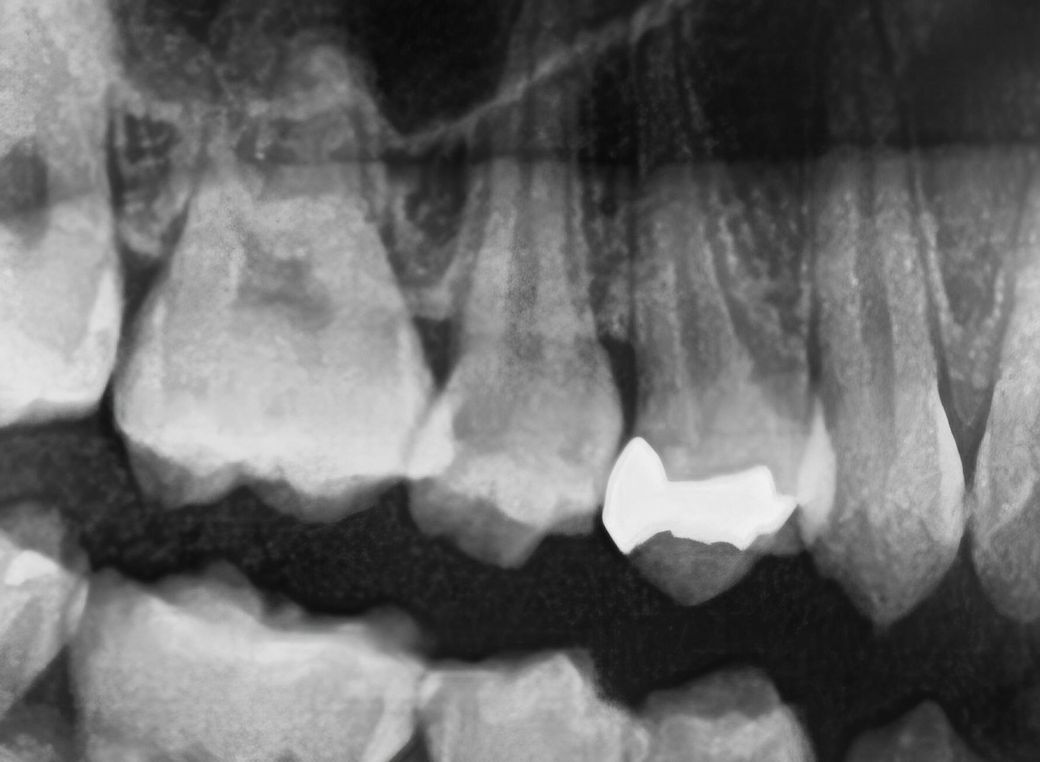

사진에서 가운데에있는 치아 신경치료 하라고 했는데

통증이 없어서요 신경치료는 되도록이면 안하는게 좋다고 하던데 어떻게할까요.. 꼭 해야할까요 ㅠ

보다 세밀한 작은 치근단 엑스레이 사진을 찍어봐야 판단이 되겠으나 충치가 있는걸로 보입니다 충치가 있다고, 깊다고 무조건 통증이 있는건 아니고 사람마다 케이스마다 다릅니다